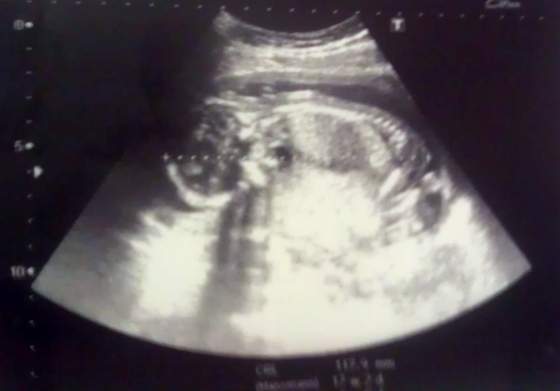

Załączniki

a oto Łusia

)) moja wymarzona, wyczekana córeczka

Brandy, Twoja dzidzia ma 118 mm, czyli w przybliżeniu 12 cm

DD ale i tak duża